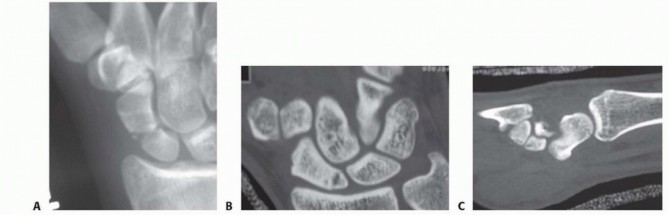

DEFINITION Fracture of the radial shaft with an associated distal radioulnar joint (DRUJ) dislocation (FIG 1A…